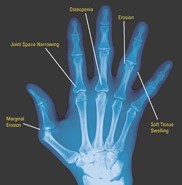

Other - X ray of the joint

What are the key investigation findings?